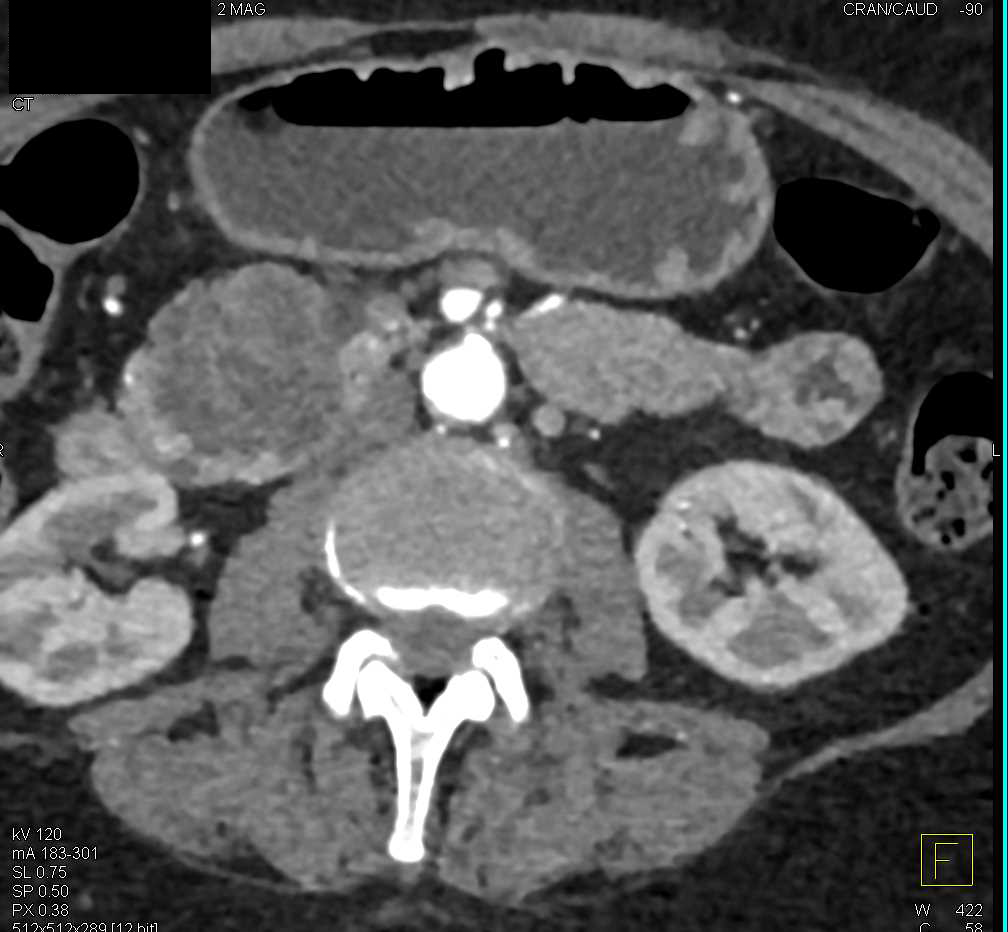

Multiple Intraductal Papillary Mucinous Neoplasms (IPMNs) in the Pancreas